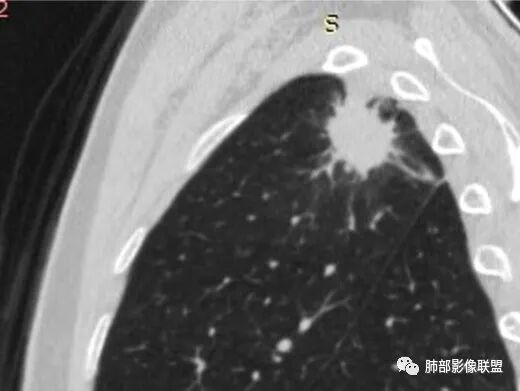

边缘收缩均匀、U型凹陷、内有小点状钙化、桃尖征

支持炎性放前面、

不放心的是部分区域膨隆

2、病灶位于左肺上叶尖后段,符合肺结核好发部位。

3、病灶密度不均,可见钙化点,未显示空洞或液化。边缘收缩,U型凹陷、桃尖征、细长毛刺以及较长棘状突起。宽基底与胸膜相连,邻近胸膜广泛性增厚(未见栽赃侵入)。可见卫星病灶,周围的磨玻璃影比较松散,炎性病变征象多,符合结核的CT表现。

4、部分区域膨隆,未见支气管截断,肺门纵隔未见肿大淋巴结等,恶性征象少。